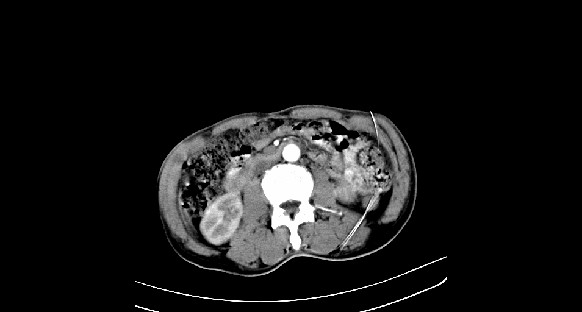

男性,70岁,体检b超发现左肾占位,请各位战友发表一下观点

左肾有两个病灶,且较大的病灶内可见点状钙化灶,增强扫描边缘也是呈渐进性强化,中央部分未见明显强化

肾癌较肾aml可能大,建议mri,若t2明显高信号者则肾癌基本诊断明确。